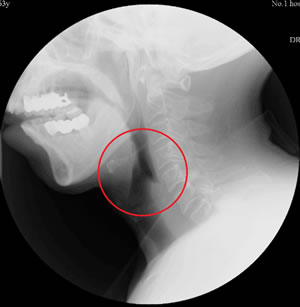

治疗前吞咽造影显示食物大量残留在梨状窦 治疗后吞咽造影显示食物已全部咽下,未见

及喉腔,环咽肌不开放 明显残留